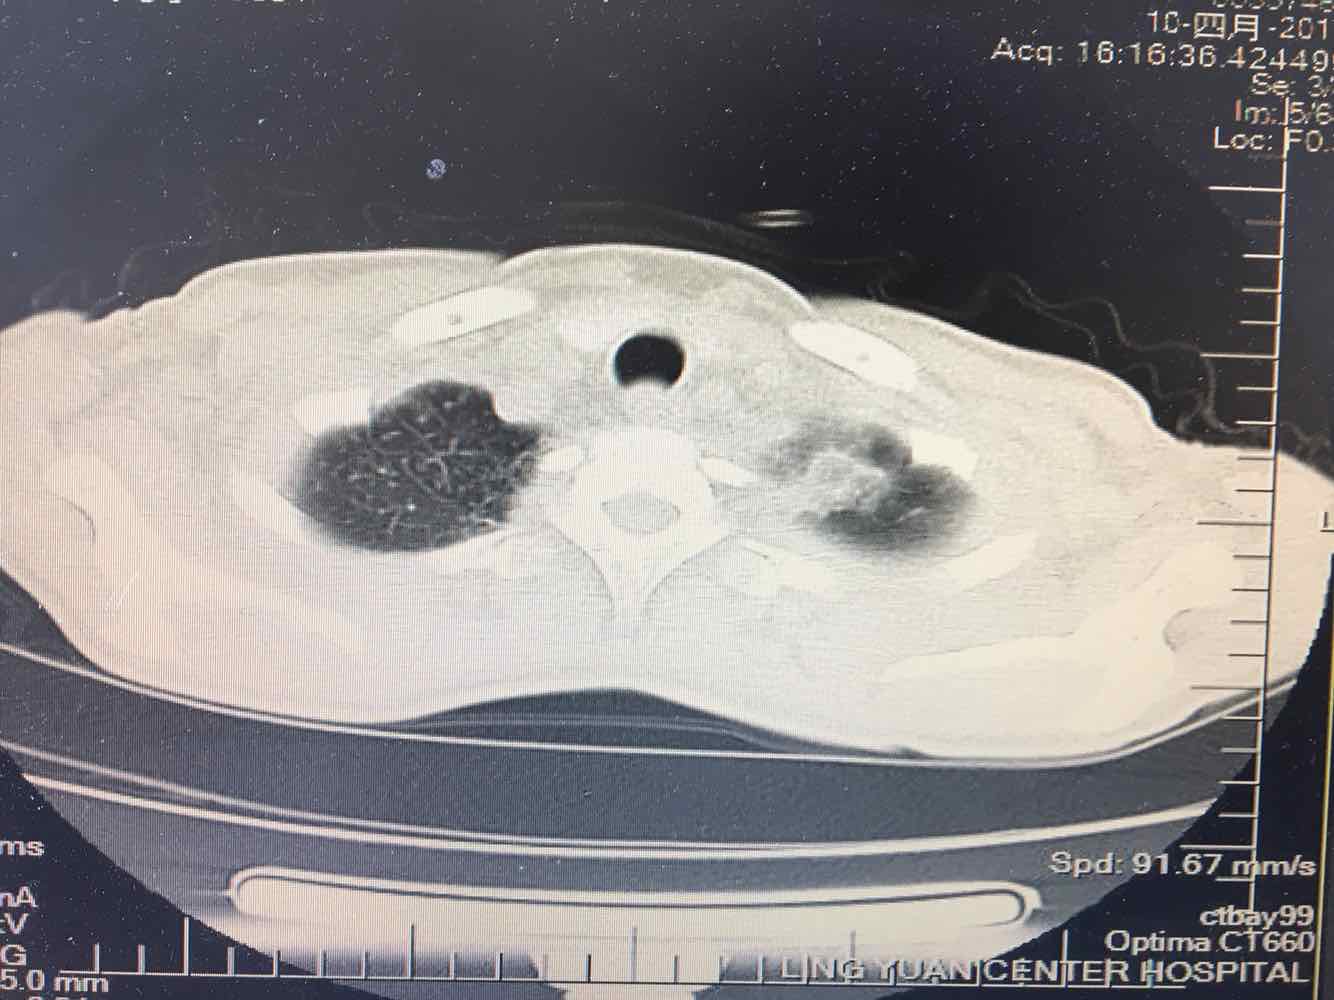

女,51岁,支气管扩张病史多年。慢性咳嗽咳痰喘息30年,加重1个月,无发热,气短为主,痰液不多,上腹不适,少尿。双肺干湿罗音。